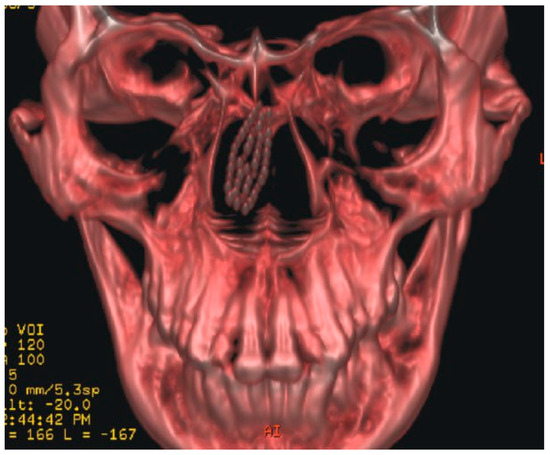

A 42-year-old woman reported to the Department of Oral and Maxillofacial Surgery with a toothbrush head lost in her nose. On careful elicitation of related events, we discovered that she had reportedly placed the tooth-brush into her nose to relieve herself of the irritable itching she was experiencing in her nose. She suffered from allergic rhinitis since childhood and frequently experienced nasal itching especially in the early morning hours. In this instance, she slipped on a wet floor and the resultant fall caused the tooth brush to snap into two pieces leaving the brush head inside the nose. The accident caused profuse nasal bleeding, which was controlled by the patient with finger pressure using a handkerchief. A computed tomographic (CT) evaluation was undertaken at a radiodiagnosis center (Figure 1) on the recommendation of a primary health care facility she had visited initially. An attempt was made at the primary health center to retrieve the brush head with a curved hemostat, which proved unsuccessful and led to a further episode of epistaxis. She was then referred to our center. She was brought to our department 3 hours after the accident. Visual inspection of the nasal cavity revealed right-sided vestibulitis with clotted blood in the right nasal cavity. The toothbrush head could not be seen on visual inspection with a nasal speculum and headlamp. Visual inspection of the pharynx was unremarkable. The patient did not complain of right nasal obstruction. The patient confirmed that she had not swallowed any portion of the object. The CT showed the presence of the toothbrush head in the superior right nasal cavity at the junction between the lateral and medial nasal walls. The brush head had caused a deviation of the nasal septum to the left (Figure 2). The patient was prepared for nasal endoscopy. The right nasal cavity was sprayed with a local anesthetic aerosol agent (lidocaine USP 15%, ICPA Health Products Ltd., Mumbai, India) and phenylephrine 0.25% applied on a cotton pellet. After 5 minutes, an endoscope was introduced into the right nasal cavity and showed a large wound in the upper part of the nasal cavity with clotted blood on the surface. No object could be identified in the nasal cavity. The patient was prepared for surgery under regional anesthesia. The patient was placed in a supine position with the head elevated ~20 degrees. The forehead, nose, and face were prepared with an antiseptic solution (2% cetavlon followed by alcohol). The nasal cavities were packed loosely with 1-cm ribbon gauze soaked in 4% lignocaine for 15 minutes. Anesthesia of the external nose was achieved using bilateral infraorbital nerve blocks (lignocaine 2% with 1:200,000 adrenaline, Xicaine, ICPA Health Products Ltd., Mumbai, India) with additional infiltrations at the base of the columella, the dorsum of the nose, the infratrochlear nerve, and the external nasal nerves, and about 0.5 mL of the solution was injected into the membranous septum. An open rhinoplasty approach with a transcolumellar extension was used. A marginal incision along the caudal border of the lateral crura of the lower lateral cartilages was made and carried medially and inferiorly along the cephalic border of the medial crus up to its lower part and then extended with a right angle turn to the caudal margin of the medial crus. A combination of sharp and blunt dissection was used to expose the entire nasal skeleton up to the nasal bones. The object was found to be lodged between the upper-right lateral cartilage and the nasal septum, with its bristles embedded into the right-upper lateral cartilage and the nasal septum (Figure 3). Dissection of the object from between the upper lateral cartilage and the nasal septum was performed after incising the upper-right lateral cartilage submucosally from the nasal cartilage and then proceeding with the exposure of the nasal septal cartilage. The object was delivered in one piece (Figure 4). Hemostasis was achieved with the use of electrocautery where indicated. Closure of the wound was achieved with polyglycolic acid 910 for the nasal mucosa and the nasal cartilages. Skin closure was achieved with prolene sutures. Bilateral nasal packs were placed. No intraoperative or postoperative complications were witnessed, and the patient was discharged on the third postoperative day.

Figure 1. Coronal computed tomography image showing position of the foreign body.